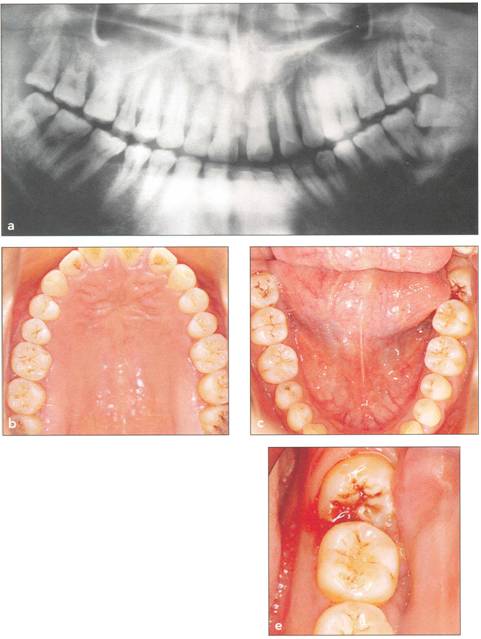

Fi 545e45f g 5-1a Preoperative panoramic view. The patient is a 24-year-old female. Transplantation of the mandibular right third molar to the area of nonrestorable mandibular first molar is planned. |

Fi 545e45f gs 5-1b and 5-1c Maxillary and mandibular teeth after initial periodontal treatment of brushing, scaling, and root planing. |

Fi 545e45f g 5-1d Preoperative periapical radiograph. |

Fi 545e45f g 5-1e Preoperative view of the donor tooth and the recipient site. |